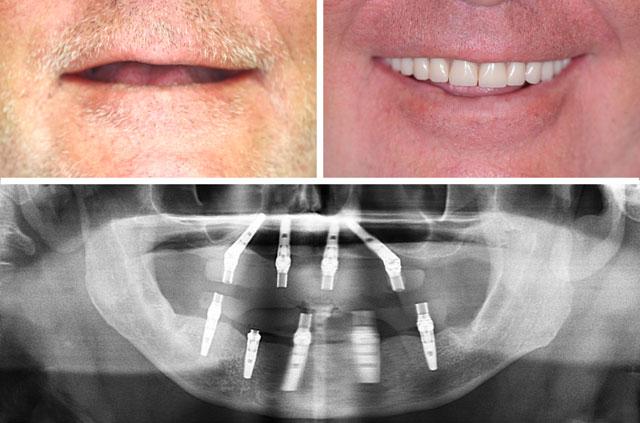

Real before-and-after results from single-tooth implants, All-on-4, All-on-6, and full-arch reconstruction cases.

Each case demonstrates the transformative power of dental implants, from single tooth replacement to full-arch restoration. Our All-on-4 Teeth-In-A-Day technique provides immediate results and long-term stability.

Custom-designed teeth that match your facial features and provide a natural appearance

All-on-4 is a revolutionary dental implant technique that uses just four strategically placed implants to support a full arch of replacement teeth. The posterior implants are angled at 30-45 degrees to maximize bone contact and avoid anatomical structures like the maxillary sinus or inferior alveolar nerve. This innovative approach allows for immediate loading with a temporary prosthesis, providing same-day teeth and eliminating the need for lengthy healing periods between procedures.